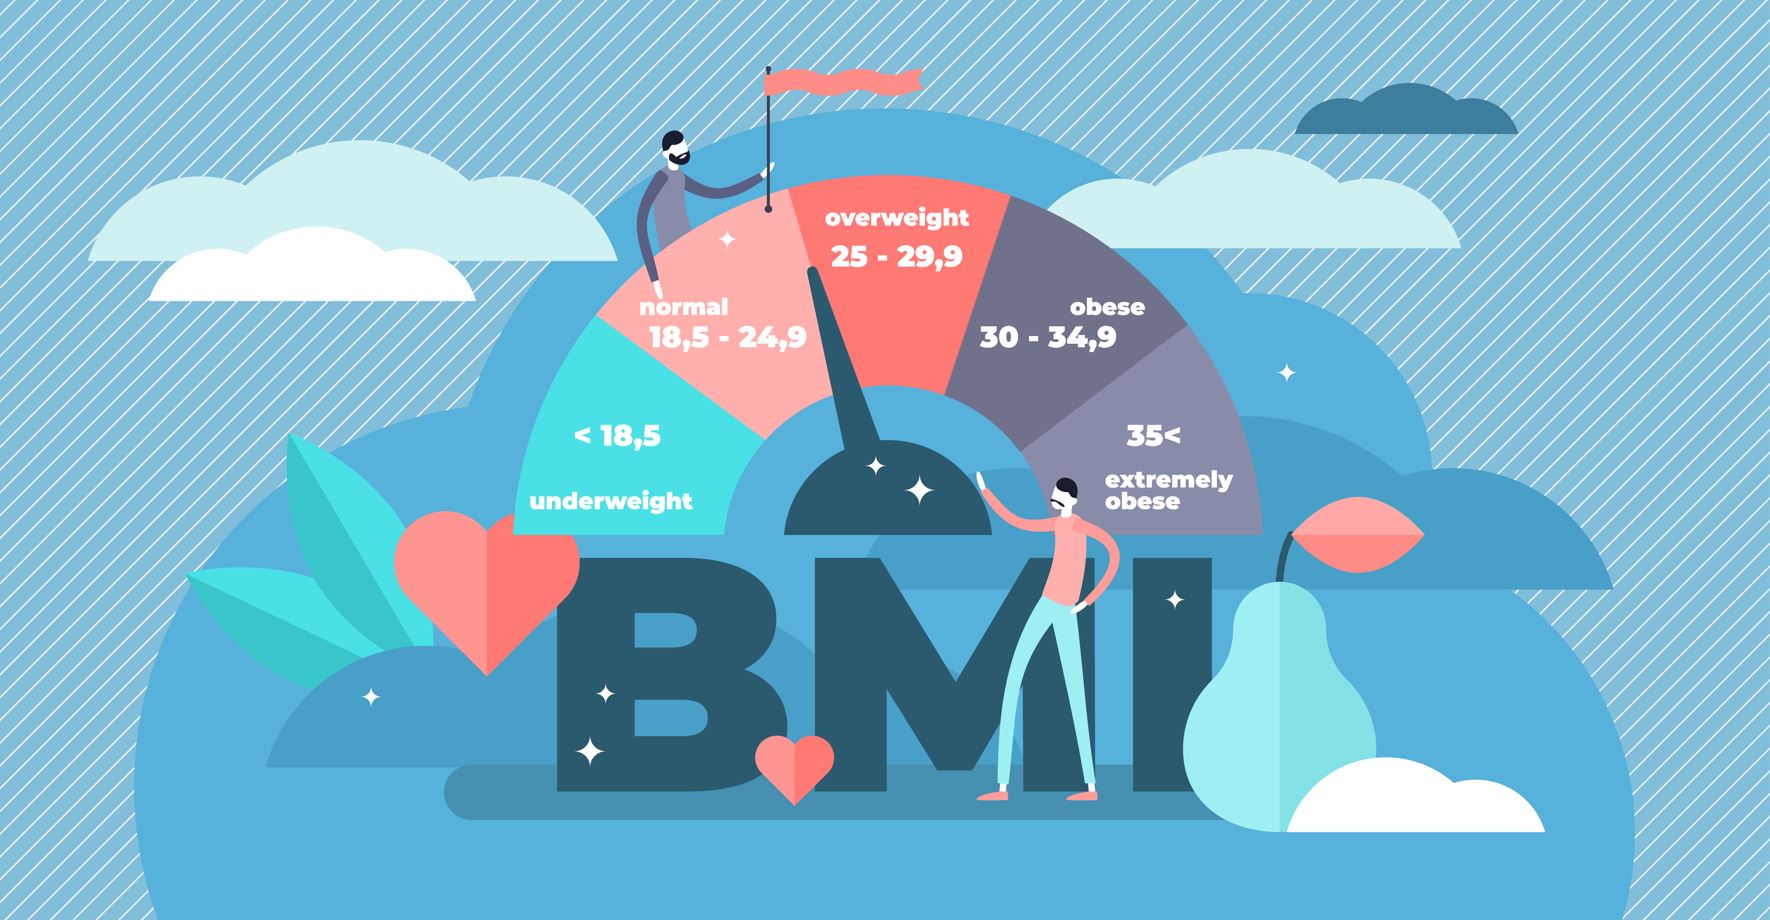

Az edukáció olyan fontos kérdéseket érint, mint: mi számít meddőségnek, mikor érdemes szakemberhez fordulni, hogyan hat az életkor a termékenységre, illetve milyen kockázatot jelentenek a szexuális úton terjedő fertőzések. Az iránymutatás külön kitér a legfontosabb kockázati tényezőkre, mint a dohányzás, a túlzott alkoholfogyasztás, az elhízás vagy éppen az alultápláltság, melyek mind kedvezőtlenül hathatnak a reproduktív egészségre. Ezzel szemben a kiegyensúlyozott, tápanyagokban gazdag étrend, a rendszeres testmozgás, valamint a dohányzás elhagyása bizonyítottan hozzájárulhat a termékenység megőrzéséhez és a későbbi problémák megelőzéséhez.